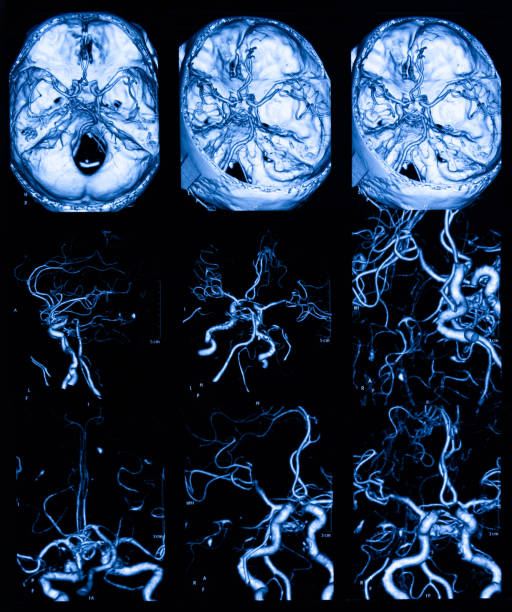

고혈압은 뇌출혈의 가장 큰 원인으로 볼 수 있는데 고혈압 환자라면 혈압이 갑작스럽게 상승하는데 이 때 산소와 영양소가 뇌로 들어가는 통로인 혈관에 변화를 일으키는데 혈관이 버티지 못하고 터지게 됩니다. 뇌동정맥의 기형에 의한 뇌출혈, 뇌동맥류 파열에 의하여 나타나며 잦은 흡연이나 다른 질병의 합병증으로 인해 발생할 수 있으며 뇌손상은 팔, 다리, 심하면 얼굴등 신체 일부분이 평생 마비시키며, 골든타임을 놓칠 경우 사망할 수도 있어 뇌출혈 전조증상에 대해 알고 있는 것이 좋습니다.